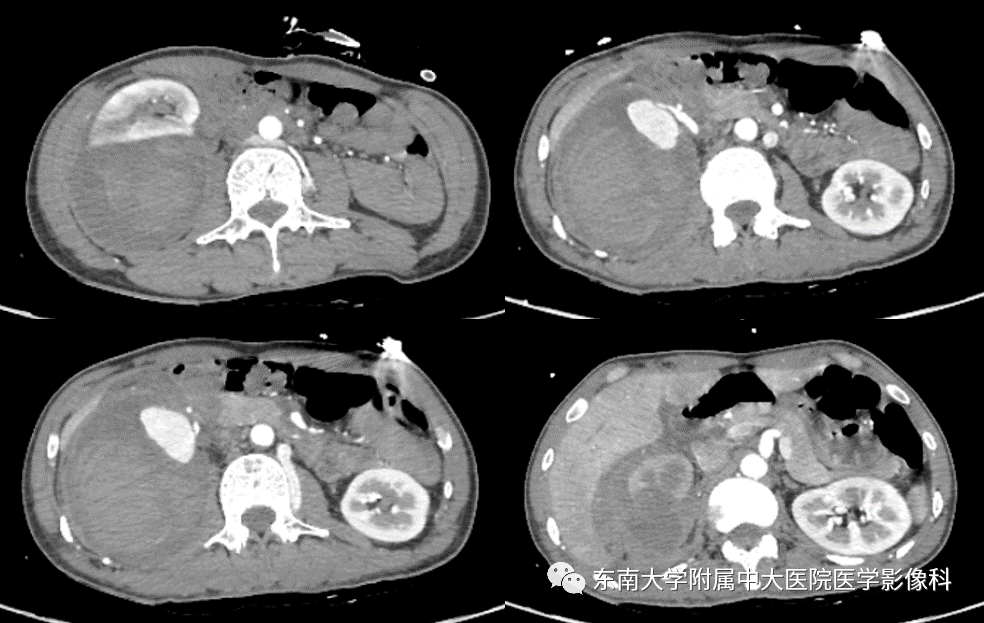

病史 男,46岁,因"外伤后右侧腰部疼痛1月"入院 ct 增强